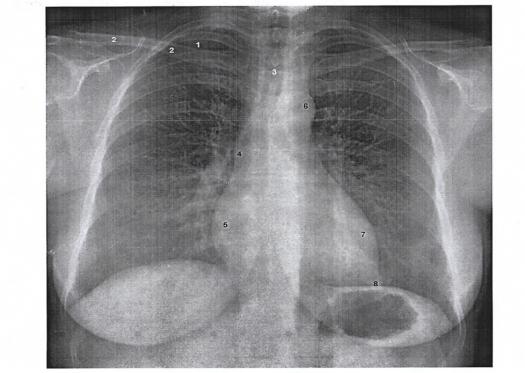

1. The part number 6 represents:

Explanation

The correct answer is descending thoracic aorta. This is because the descending thoracic aorta refers to the part of the aorta that extends downward from the arch of the aorta, through the thoracic cavity, and into the abdominal cavity. It carries oxygenated blood from the heart to the lower parts of the body. The other options, ascending thoracic aorta, pulmonary artery, and arch of the aorta, do not accurately represent part number 6.

8. The part number 3 represents:

The correct answer is Tracheal shadow. In the given options, the part number 3 represents the tracheal shadow. The trachea is a tube-like structure that carries air to and from the lungs. It appears as a dark shadow on imaging studies such as X-rays. Therefore, option 3 is the correct representation of part number 3.

The part number 6 represents:

The part number 3 represents: